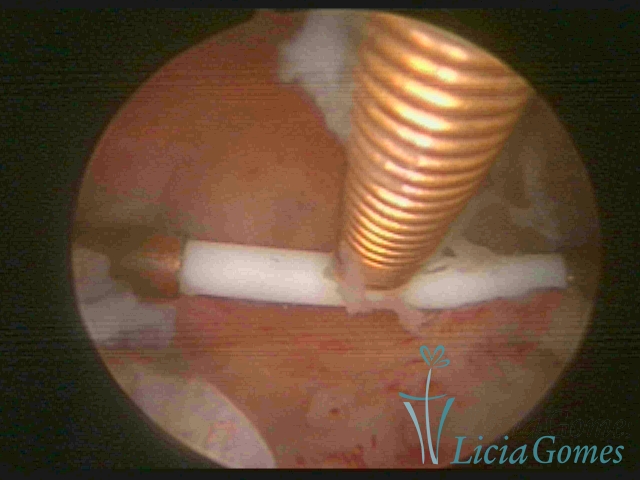

Cesarean section scar with a non-absorbed suture, as a foreign body